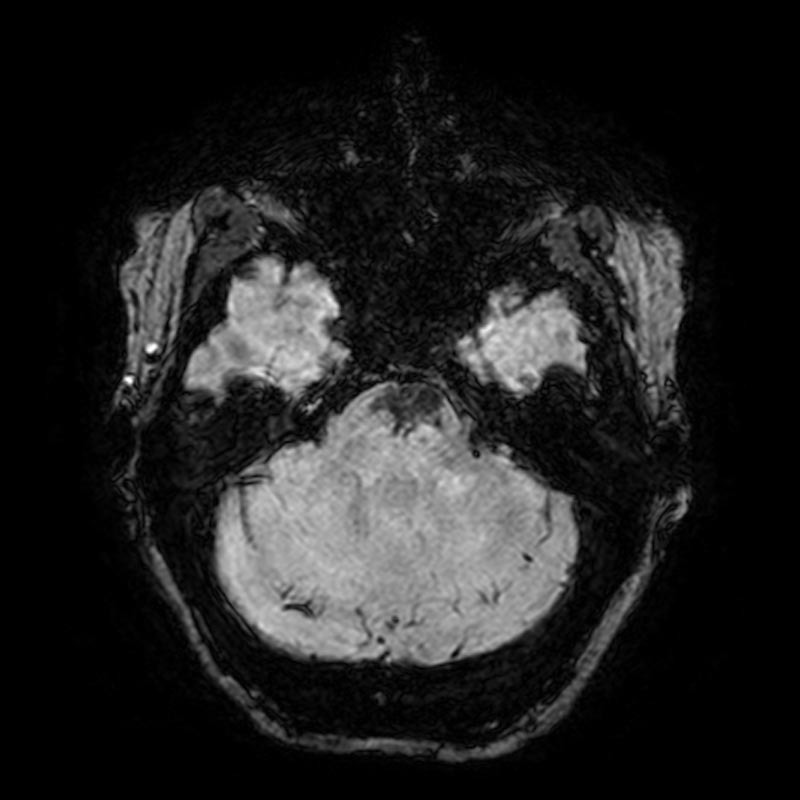

Note the multiple sites of oedema and haemorrhage, involving the brain stem and corpus callosum as well as subcortical white matter and left cerebral peduncle. High FLAIR signal is also seen in the dorsal midbrain. EVD insitu.

Case Discussion

Diffuse axonal injury can be subtle on CT but have devastating consequences for the patient. This is a case of grade III injury (involvement of brainstem) and carries a poor prognosis.

Diffuse axonal injury (DAI), also known as traumatic axonal injury (TAI), is a severe form of traumatic brain injury due to shearing forces. It is a potentially difficult diagnosis to make on imaging alone, especially on CT as the finding can be subtle, however, it has the potential to result in severe neurological impairment.

The diagnosis is best made on MRI where it is characterised by several small regions of susceptibility artifact at the grey-white matter junction, in the corpus callosum, and in more severe cases in the brainstem, surrounded by FLAIR hyperintensity.

Diffuse axonal injury is characterised by multiple focal lesions with a characteristic distribution: typically located at the grey-white matter junction, in the corpus callosum and in more severe cases in the brainstem (see: grading of diffuse axonal injury).

MRI is the modality of choice for assessing suspected diffuse axonal injury even in patients with entirely normal CT of the brain 5,6. MRI, especially SWI or GRE sequences, exquisitely sensitive to paramagnetic blood products may demonstrate small regions of susceptibility artefact at the grey-white matter junction, in the corpus callosum or the brain stem. Some lesions may be entirely non-haemorrhagic (even using high field strength SWI sequences). These will, however, be visible as regions of high FLAIR signal.

Over the first few days, the degree of surrounding oedema will typically increase, although by 3-months post-injury FLAIR changes will have largely resolved 7. In contrast, SWI changes will usually take longer to resolve, although by 12-months post-injury there will have been substantial resolution 7. This is to be expected as oedema is faster to resolve than haemorrhage.